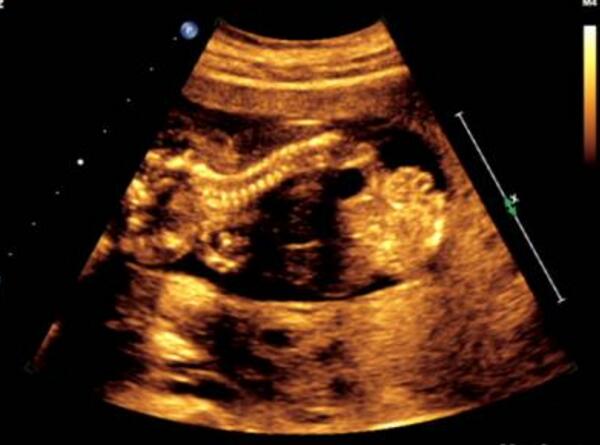

子宫纵膈是一种女性先天性的子宫发育异常疾病,是由于双侧副中肾管融合后,中隔吸收的某一过程受阻,导致不同程度的纵隔子宫。根据分隔宫腔程度的不同可分为完全子宫纵膈和不完全子宫纵膈。

完全子宫纵膈指的是中隔自宫底一直延伸至宫颈内口的情况。

不完全子宫纵膈指的是中隔从宫底延伸,但未达到宫颈内口水平,只是将宫颈部分隔开的情况。